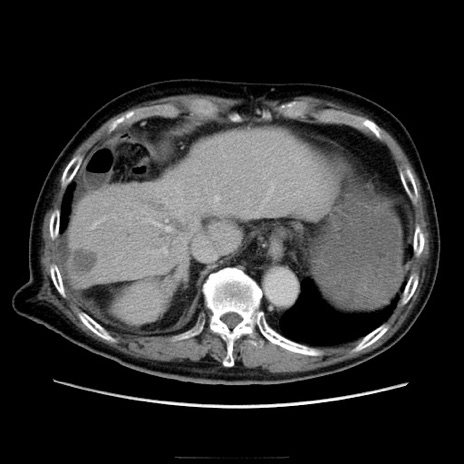

症例21(横断像)

【症例】70歳代男性

【主訴】腹痛

【現病歴】肝硬変・肝細胞癌にてかかりつけの方。約9時間前に食後より腹痛出現。症状が徐々に増悪し、嘔吐出現したため来院。

【既往歴】肝硬変、肝細胞癌(RFA、TACE後)

【身体所見】意識清明、表情苦悶様、BT 36℃、BP 129/78mmHg、P 88bpm、SpO2 97%(RA)、右上腹部から心窩部にかけて圧痛あり、反跳痛なし、筋性防御あり。

【データ】WBC 5800、CRP 0.16